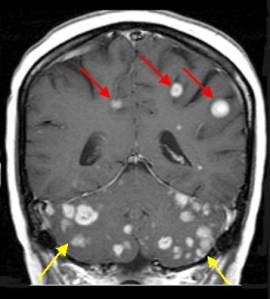

Brain metastases are relatively common in lung cancer, seen in about 15% of cases, and the management of them is evolving as technology and our preferences change. For decades, whole brain radiation therapy (WBRT) was the only game in town and did a reasonable job controlling a problem that we couldn’t manage readily any other way – chemotherapy generally doesn’t penetrate well into the brain, and brain surgery is only a feasible option for one or a few brain metastases, not many.

But over the past 10-15 years, stereotactic radiosurgery (SRS), which is more broadly known by the marketed names Gamma Knife or Cyber Knife, became more readily available and better studied. It has become a standard of care for patients with 1-3 brain metastases, and increasingly offered and used for far more brain metastases, as WBRT became more feared for its potential to cause short- and long-term cognitive problems. While long-term cognitive function was not a significant concern many years ago, when survival was far more limited, it has become a more relevant and dreaded concern as more patients with lung cancer are living well beyond prior benchmarks.

The second trial, known as NCCTG N0574, was actually presented in the ASCO 2015 Plenary Session and addressed the question of whether WBRT provided additional benefit that more than counterbalanced the risks of it in 213 patients, 72% with lung cancer, who also received SRS for 1-3 brain metastases. On this trial, there was also no significant difference in survival between the treatment arms, while cognitive function was worse in patients with WBRT (92% vs. 64% with cognitive decline 3 months later, for SRS alone or with WBRT, respectively). On the other hand, progression with new or enlarging brain metastases was significantly more common with SRS alone at 3 months (25% vs. 6%) and 6 months (35% vs. 12%).